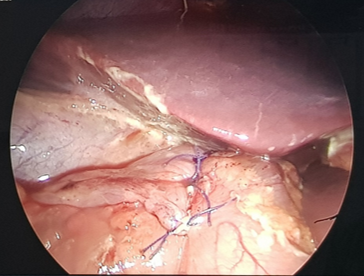

dày, bằng kinh nghiệm và tay nghề của bác sĩ phẫu thuật, bệnh nhân đã được khâu

đóng lỗ thủng, làm sạch ổ bụng.

Sau khâu lỗ thủng dạ dày